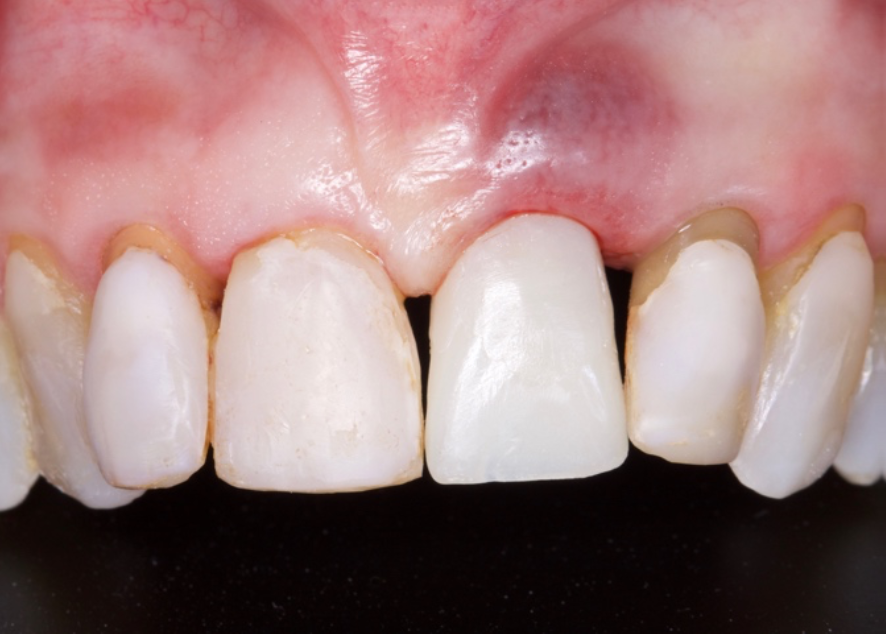

O objetivo deste relato de caso é mostrar a utilização do implante de diâmetro reduzido em região anterior de maxila com limitação óssea, respeitando a anatomia do processo alveolar e consequentemente utilizando um componente angulado para corrigir a posição da saída do parafuso para confecção de uma prótese aparafusada.

Conforme discutido na literatura, a colocação imediata de implantes na zona estética requer que o clínico tenha conhecimento e experiência em diversas áreas. Isso inclui diagnóstico estético, técnicas de extração minimamente invasivas, procedimentos cirúrgicos plásticos orais (por exemplo, enxerto de tecidos duros e moles) e colocação de implantes tridimensionais (3D) precisos com o uso de um implante mais estreito (3,3 mm a 4,3 mm), o que garante um espaço vestibular de pelo menos 2 a 3 mm adjacente à parede do alvéolo bucal intacto. Isso pode ser pré-planejado com uma análise cuidadosa através de exames de imagem para uma melhor compreensão do plano restaurador. O uso de técnicas avançadas de imagem, como a tomografia computadorizada de feixe cônico (CBCT), pode auxiliar no planejamento preciso do tratamento e na colocação do implante.

O planejamento no tratamento de implante imediato deve incluir uma avaliaçãocompleta do alvéolo de extração, osso circundante e tecidos moles. Essa avaliação ajuda a determinar o tamanho, o tipo e a técnica de colocação do implante.